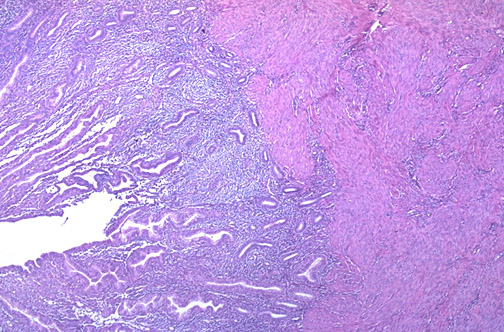

| At low power the uterus has a myometrium composed of smooth muscle bundles supporting the basalis layer of endometrium from which the endometrium regenerates with each menstrual cycle. Above the basalis is the functionalis layer, seen here as secretory phase endometrium. |